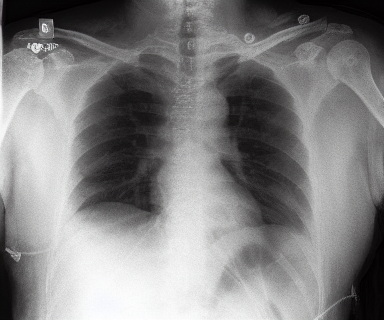

We present the results of conditional medical image generation with and without our proposed method LD, in Tab. 1, and Fig. 5. In Fig. 4, we show examples of brain MR images generated by the different methods combined with LD for two different classes of cognitively normal (CN) and Alzheimer’s disease (AD). The results were obtained by fine-tuning the corresponding method on the medical data with LD. As shown in Fig. 4, the samples generated through Custom Diffusion tuning are realistically looking while understanding the difference between CN and AD brain properly, which other methods failed at. Textual inversion seems to understand the concept but fails to understand the brain structure properly. Quantitative results on the performance of all our methods are presented in Tab. 1. Qualitative results on the CheXpert [19] dataset, along with a user study and ablation of different parameters, optimization algorithm, and more, are included in the supplementary material.

Qualitatively, Fig. 5 shows a significant improvement of the visual realism across all methods when using a drift of . The background is consistently black as in real brain MR images; the shape of the brain becomes more realistic, and the white and gray matter structure improves. For an analytical evaluation, we calculated the FID between our test data and 200 synthetically generated images from each method (100 CN, 100 AD). The results in Tab. 1 demonstrate that LD improves the ability of the model to generate realistic MRI slices for both healthy brains and brains with Alzheimer’s disease. For this reason, all following experiments were done with LD.